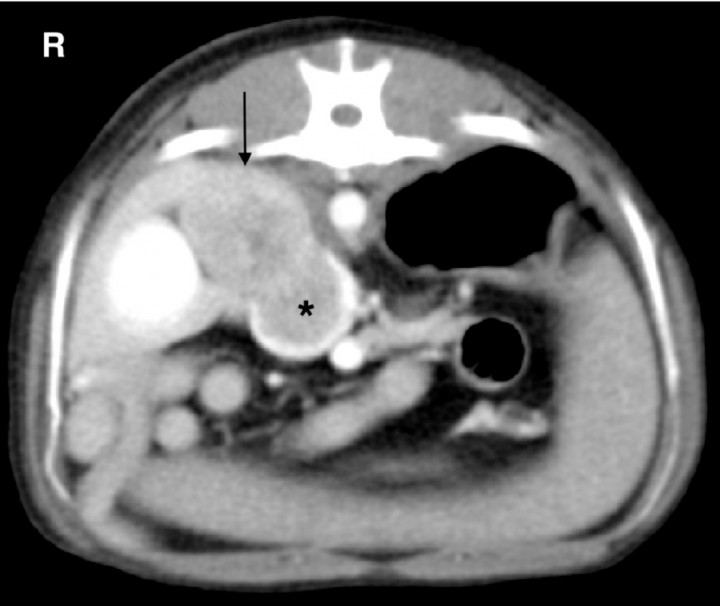

Primary neoplasia of the canine adrenal gland includes adenoma, carcinoma and pheocromocitoma. CT imaging of adrenal masses is especially useful to detect adjacent vascular invasion to assess the resectability of the mass but it is not capable of delineating tumor type. Adrenal masses can contain mineralizations and cystic regions, and can show peripheral rim enhancement representing fibrous encapsulation, or a heterogenous contrast enhancement in delayed postcontrast CT images associated with haemorrhage or infarction. The proximity of the adrenal gland to the caudal vena cava predisposes to vascular invasion of the phrenic and caudal vena cava veins and the formation of thrombus (Fig. 8).[ Gregori T, Mantis P, Benigni L et al.: Comparison of computed tomographic and pathologic findings in 17 dogs with primary adrenal neoplasia. Vet Radiol Ultrasound 2015; 56:153-159. [PubMed] ]

<p>Adrenal gland carcinoma with severe invasion of the caudal vena cava. CT angiogram transverse image in soft tissue window. Note the large mass at the level of the right adrenal gland (arrow) and the large filling defect within the caudal vena cava (black asterisk) at the same level. R: right.</p>

Adrenal gland carcinoma with severe invasion of the caudal vena cava. CT angiogram transverse image in soft tissue window. Note the large mass at the level of the right adrenal gland (arrow) and the large filling defect within the caudal vena cava (black asterisk) at the same level. R: right.